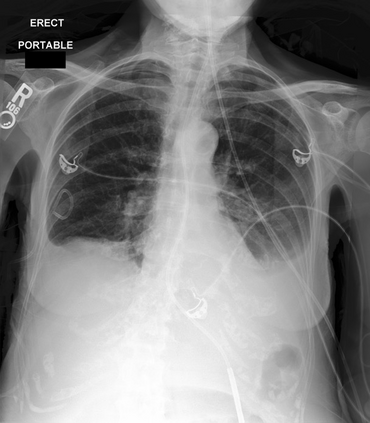

To address these issues, we propose a novel Adaptive patch-word Matching (AdaMatch) model to correlate chest X-ray (CXR) image regions with words in medical reports and apply it to CXR-report generation to provide explainability for the generation process. AdaMatch exploits the fine-grained relation between adaptive patches and words to provide explanations of specific image regions with corresponding words. To capture the abnormal regions of varying sizes and positions, we introduce the Adaptive Patch extraction (AdaPatch) module to acquire the adaptive patches for these regions adaptively. In order to provide explicit explainability for CXR-report generation task, we propose an AdaMatch-based bidirectional large language model for Cyclic CXR-report generation (AdaMatch-Cyclic). It employs the AdaMatch to obtain the keywords for CXR images and `keypatches' for medical reports as hints to guide CXR-report generation. Extensive experiments on two publicly available CXR datasets prove the effectiveness of our method and its superior performance to existing methods.